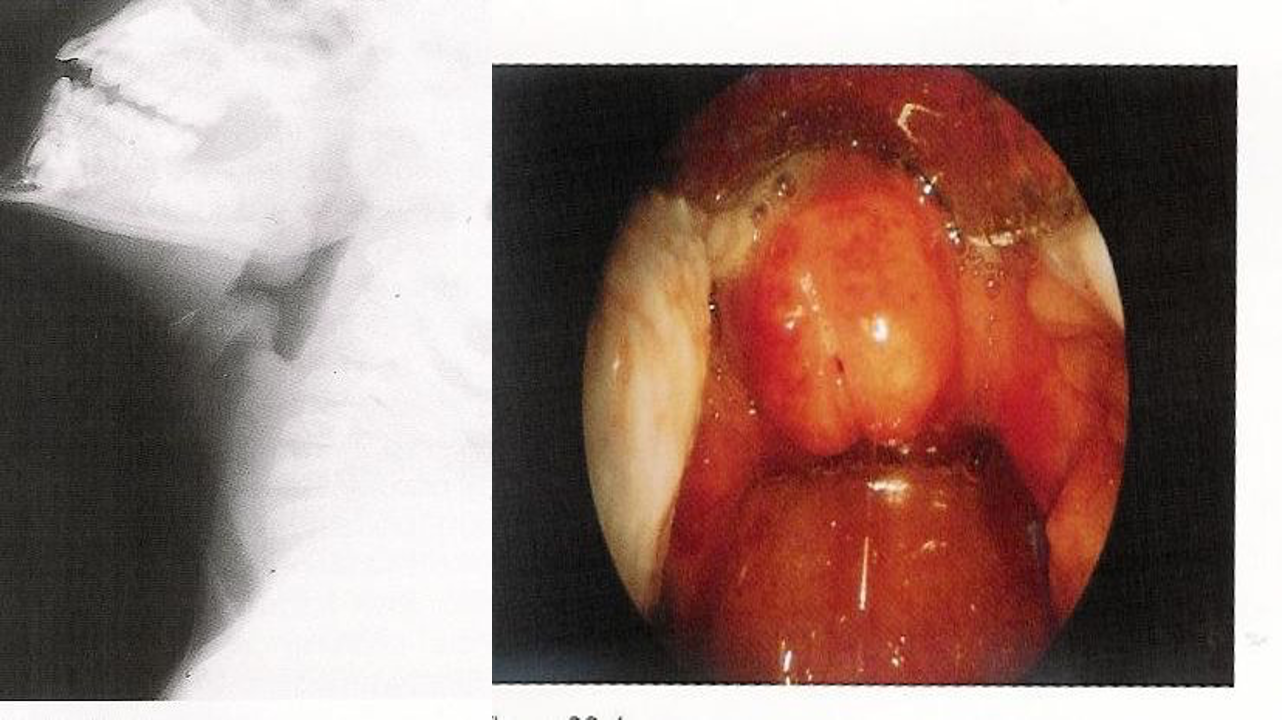

- Direct Visualization: Preferred if clinical suspicion is high. Performed during airway management in the operating suite. Shows a swollen, cherry-red epiglottis with an endotracheal tube passing posteriorly.

swollen cherry-red epiglottitis with an endotracheal tube passing posteriorly